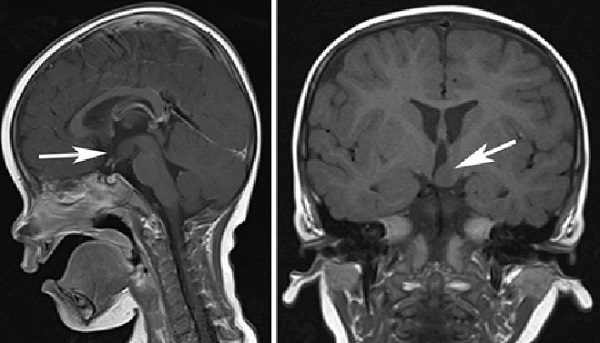

- MRIで視床下部や下垂体に腫瘍の有無を確認

視床下部過誤腫は笑い病とも呼ばれます。笑い発作は、強迫的な笑い表情、微笑、声をあげて大笑い、楽しい感じを伴わない笑いの事が多い。視床下部過誤腫が「笑いのツボ」である乳頭体を刺激するのが原因。抗てんかん薬では治りません。

けいれん発作

けいれん発作は、周囲に体をぶつけ、全身傷だらけになるので虐待と間違われる事があります。

てんかん性脳障害

てんかん発作に続発する二次的な脳障害で、早期の視床下部過誤腫治療により、てんかん発作が消失すれば改善します(早期に治療されなければ不可逆性)。

精神発達遅滞

精神発達遅滞が起きる前に、早期の視床下部過誤腫治療が必要です。

行動異常

視床下部過誤腫が大きいと、多動や制御の効かない行動をおこし、ADHD(注意欠陥/多動性障害) 、甲状腺機能亢進症/バセドウ病 と間違えられる事があります。

思春期早発症

サイズが大きい視床下部過誤腫は、思春期早発症を引き起こす事があります。視床下部過誤腫がLH-RHを作るのでなく、サイトカイン(生理活性タンパク)TGFα・TGFβを分泌し、正常な視床下部組織からのLH-RH分泌を促進させるためです。

視床下部過誤腫の全摘出は必要だが、早期からのホルモン療法[LH-RHアナログ、リュープロリン(リュープリン®)投与]が有効。

視床下部過誤腫の治療

視床下部過誤腫の治療、抗てんかん薬・ホルモン療法[LH-RHアナログ,リュープロリン(リュープリン®)投与]は対症療法に過ぎず、根治的には、視床下部過誤腫の摘出しかありません。しかし、視床下部は、脳の最も深い所にあり手術が困難です。手術後、記憶障害の後遺症もあります。